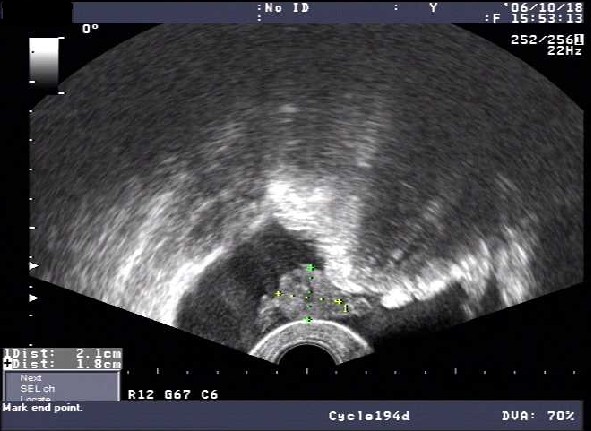

盆腔积液15mm图片

上面是“盆腔积液15mm”X光图片:是指事实上盆腔积液分为生理性和病理性,生理性的盆腔积液多发生在妇女排卵后或早孕期,多可自然消失,不必进行治疗。在临床上大多数妇女的盆腔积液是由于炎症引起,是盆腔存在炎性渗出物,如果不加以治疗的话,可以慢慢长大。那么,盆腔积液15mm严重吗?